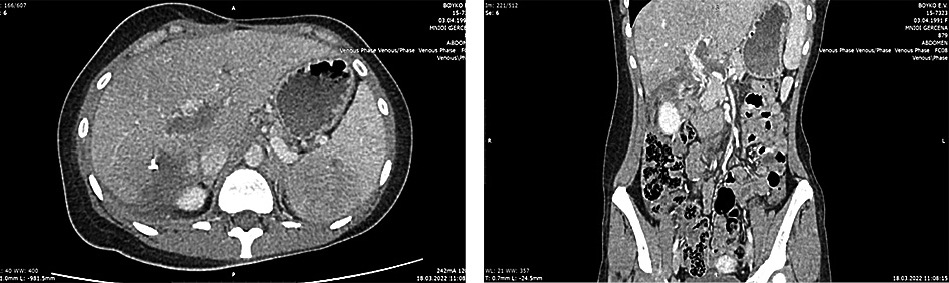

В сентябре 2022 г. проведена КТ грудной клетки, брюшной полости, таза. Отмечены постоперационные изменения левого легкого, увеличение размеров опухоли правой доли печени и протяженности опухолевого тромба в воротной вене и ее долевых ветвях. Опухолевые узлы в проекции левого надпочечника и правой почки, очаг в теле LII позвонка – без динамики. Опухолевый узел в селезенке – некоторое увеличение размеров. Множественные расширенные коллатерали воротной вены (рис. 4).

Рис. 4. КТ грудной клетки, брюшной полости, таза. Сентябрь 2022 г.

Fig. 4. CT scan of the chest, abdomen, and pelvis. September 2022.